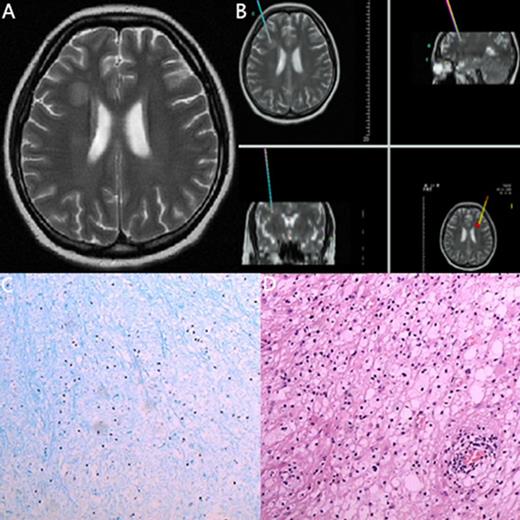

The MRI, biopsy site and pathology of a 23-year-old woman with ALL